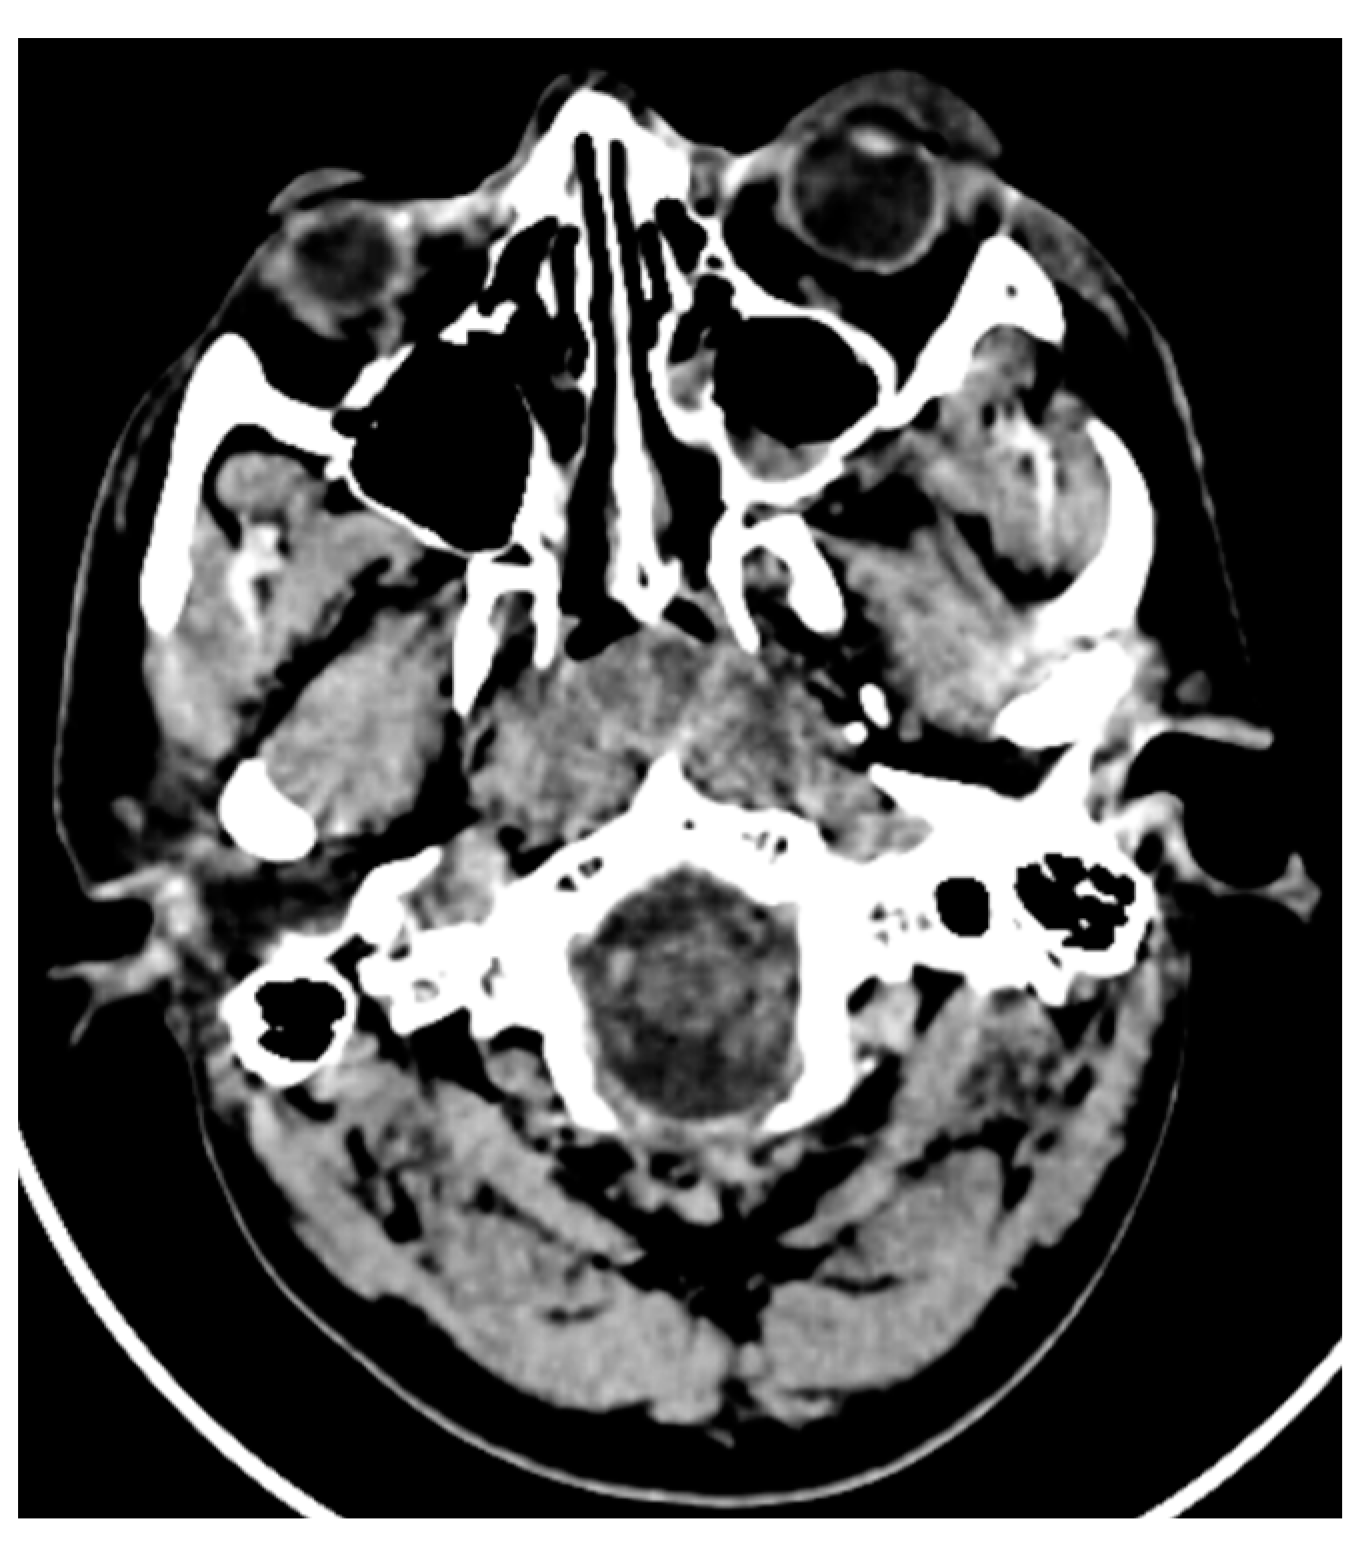

Streak and windmill artifacts greatly affect the scan images in CT. Windmill artifacts occur due to under-sampling along the Z axis, which usually occurs in the clavicle region and the base of the skull region, where drastic anatomical changes and differential Hounsfield units are present. A black streak artifact of the beam hardening effect greatly disrupting the diagnostic quality can be seen in Figure 7.

Figure 7. Black streak artifact of beam hardening effect evident in an axial section CT image. These are usually present at the base of the skull region, where drastic anatomical changes and differential Hounsfield units are present.